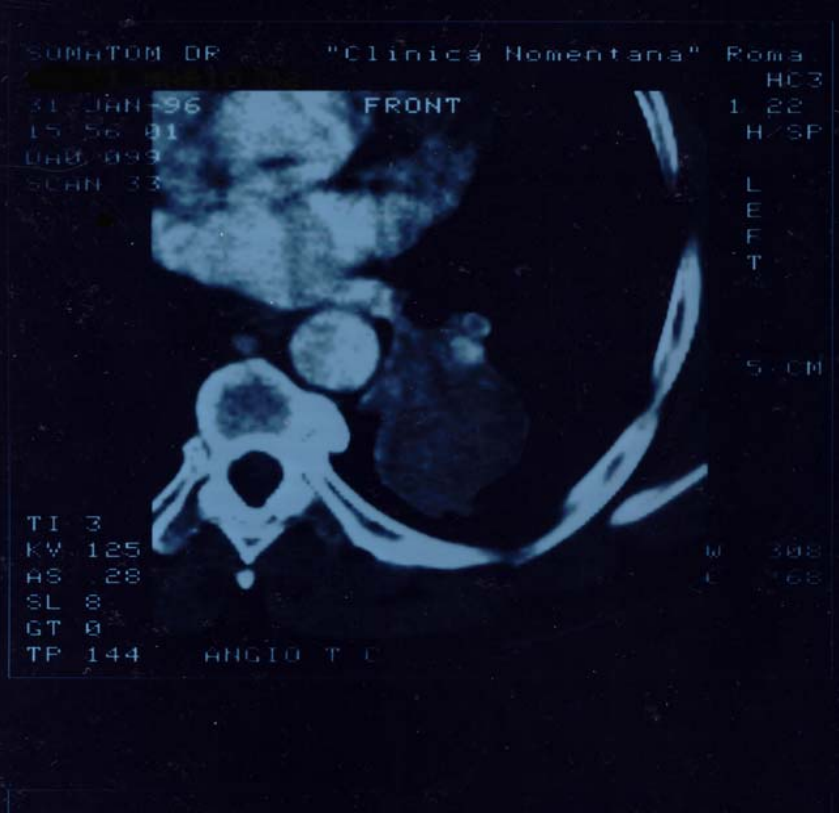

Figure2